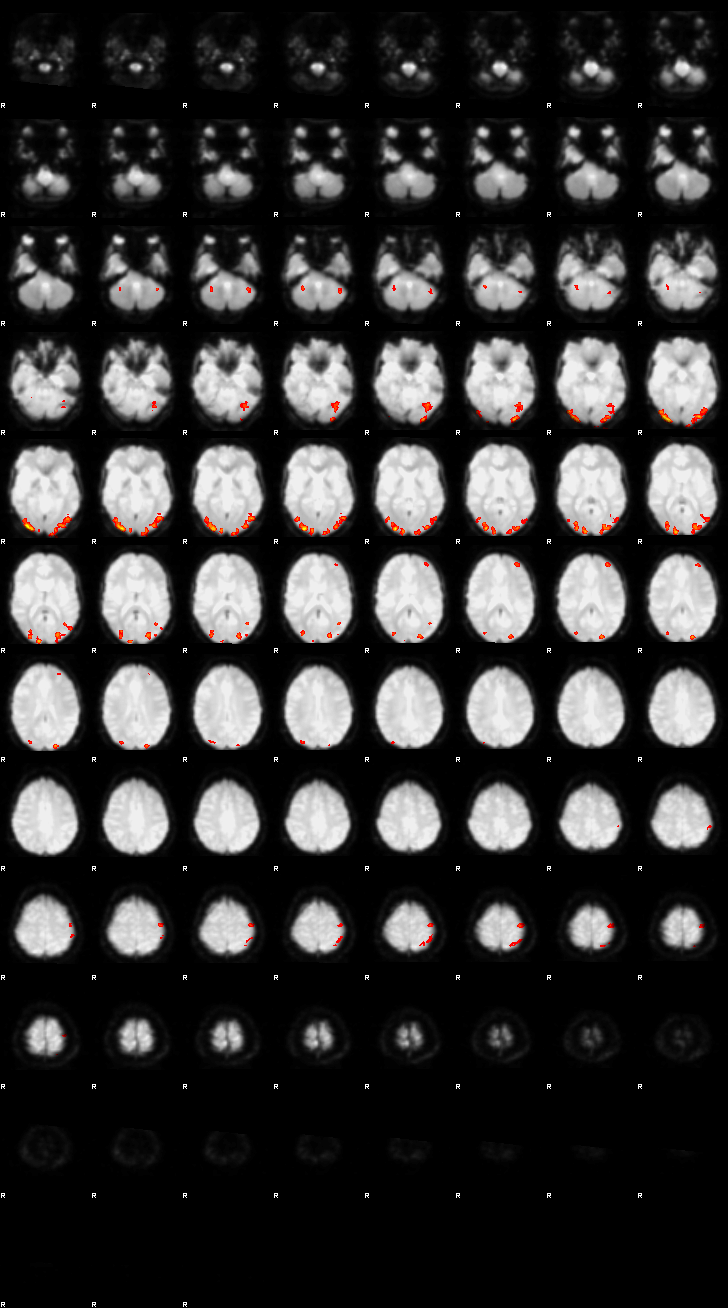

Visualization of First-level Design and Results (Run 1)#

Below, the design matrix and selected results from the first run are shown. Since both runs use the same design and contrasts, the results of the second run can be explored using the same approach.

Let’s now display the thresholded activation maps. A voxelwise threshold of Z > 3.1 was applied, followed by cluster-level correction at p < 0.05 (corrected for multiple comparisons).

zstat1 - C1 (incongruent)

zstat2 - C2 (congruent)

zstat3 - C3 (incongruent-congruent)

display(Markdown("#### Incongruent"), rendered_thresh_zstats1)

Incongruent

display(Markdown("#### Congruent"), rendered_thresh_zstats2)

Congruent

display(Markdown("#### Incongruent-Congruent"), rendered_thresh_zstats3)

Incongruent-Congruent